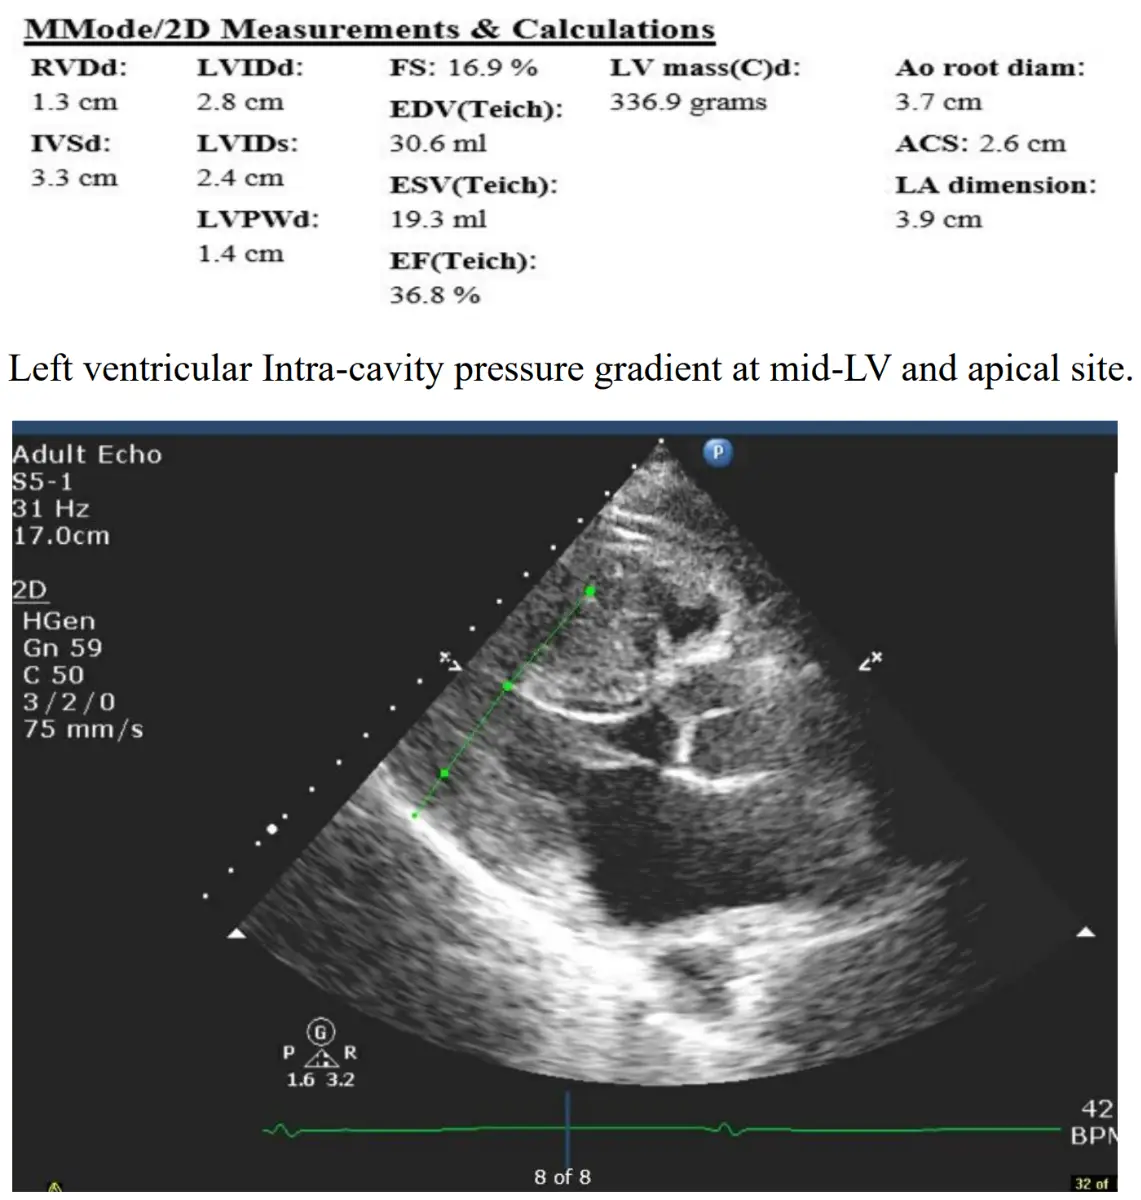

- 心臟超音波(Parasternal long-axis view)

- 室間隔厚度(IVSd)3.3 cm,後壁厚度(LVPWd)1.4 cm,septal/posterior 壁厚度比遠大於1.3,符合非對稱室間隔肥厚(asymmetric septal hypertrophy)診斷標準([pmc.ncbi.nlm.nih.gov](https://pmc.ncbi.nlm.nih.gov/articles/PMC747396